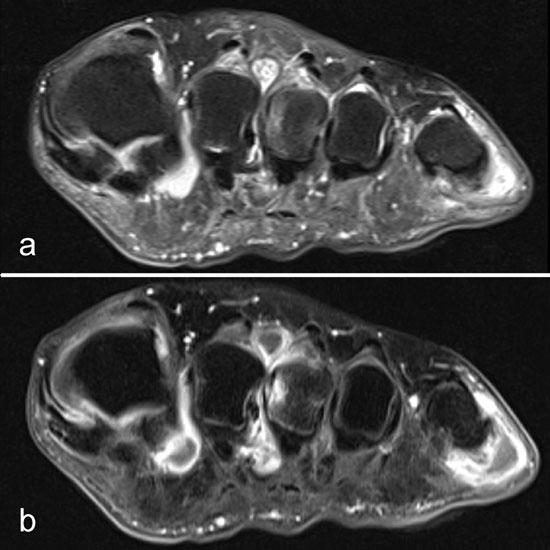

Intermetatarsale Bursitis

Intermetatarsale Bursitis bei rheumatoider Arthritis mit Erguss (a) und deutlicher Synovialitis in mehreren Schleimbeuteln (b).

Abbildung 13

Zwischen den Metatarsaleköpfchen befinden sich kleine Schleimbeutel, die in der Regel MR-tomographisch nicht zu identifizieren sind. Sie werden erkennbar, wenn sie zarte Flüssigkeitsstreifen enthalten, was noch nicht als pathologisch zu werten ist. Eine signifikante Distension und vor allem eine verstärkte Kontrastmittelanreicherung sind Ausdruck einer Bursitis. Die isolierte Bursitis intermetatarsal ist selten und stets hochverdächtig für das Vorliegen einer rheumatischen Grunderkrankung (Abb. 13).

Häufig sind intermetatarsale Bursitiden als Begleitphänomen bei Rupturen oder Degenerationen der plantaren Platte und auch bei Morton-„Neuromen“.